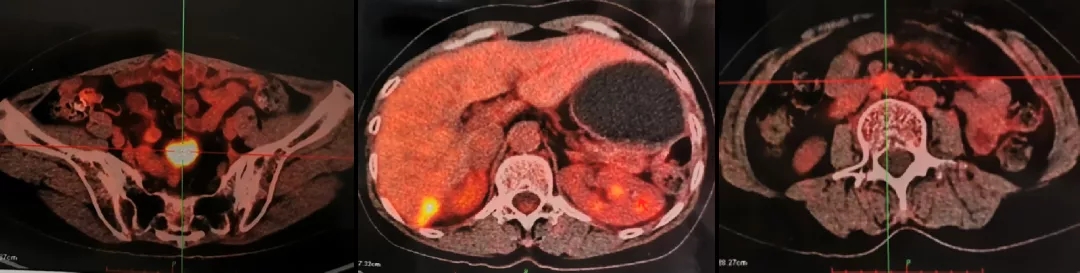

2021.4.23复查CA125上升至70.2U/ml。2021.4.24 CT:肝肾隐窝病灶增大,考虑复发。患者退出BGB-290临床试验。

2021.5.8 PET-CT:肝肾隐窝转移灶。2021.5.12复查CA125水平为95.5U/ml。

PET-CT检查结果

PARPi后线治疗获得了不错疗效,缓解持续时间达2年。目前患者已经使用过PARPi,下一步怎样治疗?

一位讨论嘉宾认为,复发后病灶依然有出现在肝肾隐窝,针对这个部分的病灶,可以考虑介入放疗;相反的观点是放疗会加重组织粘连,不利于后续的手术治疗。一位专家建议:PARPi治疗后已有2年缓解时间,可以继续化疗。另一种观点是如果患者接受,再次进行手术也有可取之处。